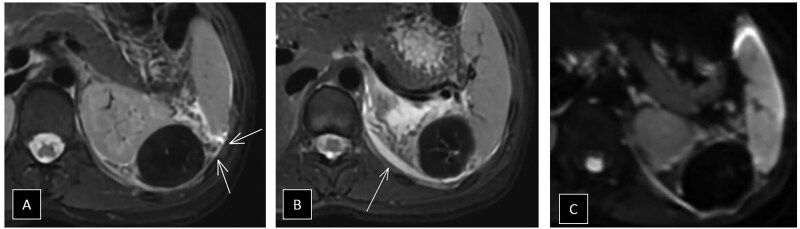

Accessory spleen torsion is a rare but important cause of acute abdominal pain, often presenting with non-specific symptoms that overlap with more common abdominal pathologies. This case report discusses a 19-year-old female who presented with left-sided flank pain and leucocytosis. Imaging with abdominal CT and MRI revealed a well-defined lesion near the spleen and kidney, with mild vascular engorgement and surrounding inflammation. While these findings raised suspicion for accessory spleen torsion, the diagnosis was not immediately clear. The lesion's location, vascular congestion, and absence of typical characteristics for other pathologies, such as haematomas, abscesses, mesothelial cysts, or lymphangiomas pointed towards torsion, but confirmation required surgical intervention. During laparoscopic exploration, a 5 cm accessory spleen with ischaemic changes due to torsion of its pedicle was identified and successfully removed without complications. Accessory spleens, present in 10%-30% of the population, are usually asymptomatic but can become problematic if torsion, rupture, or infarction occurs. Imaging plays a critical role in identifying torsion, with CT and MRI revealing the characteristic "whirlpool sign" and vascular congestion. Early recognition is crucial to prevent complications such as necrosis and rupture, and surgical intervention, typically laparoscopic splenectomy, is the treatment of choice. This case highlights the importance of considering accessory spleen torsion in the differential diagnosis of acute abdominal pain, particularly in young patients with non-specific symptoms. Awareness of this condition can improve early diagnosis and outcomes, preventing severe consequences.

Abstract Image